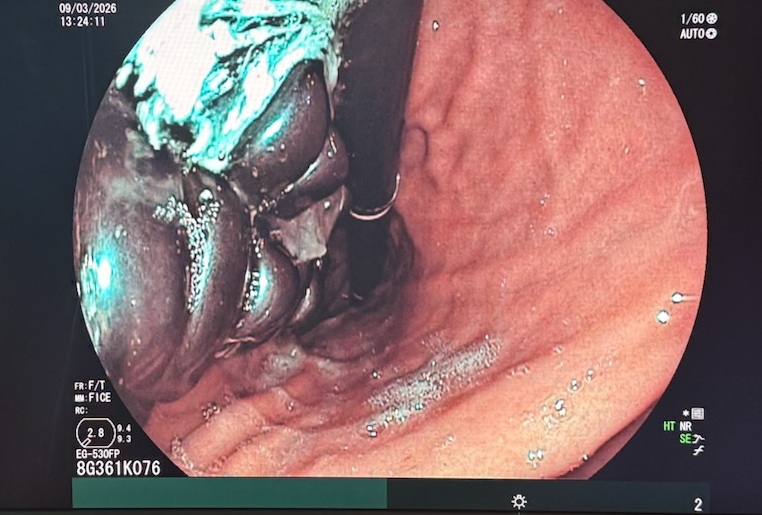

Endoszkóppal próbálkoztak

A szakorvosok endoszkópos próbálkozása nem volt elegendő, mivel az erősen összetapadt mágneseket egyenként nem lehetett eltávolítani. Végül sebészeti úton, a lehető legkisebb megterhelést jelentő módszerrel távolították el a mágneseket.

A Heim Pál kórház bejegyzése szerint a gyomrot előemelték, apró nyíláson keresztül emelték ki a tárgyakat, majd a gyomorfalat és a hasfalat zárták. A gyermek gyorsan, szövődménymentesen felépült, és hamarosan újra enni kezdett.